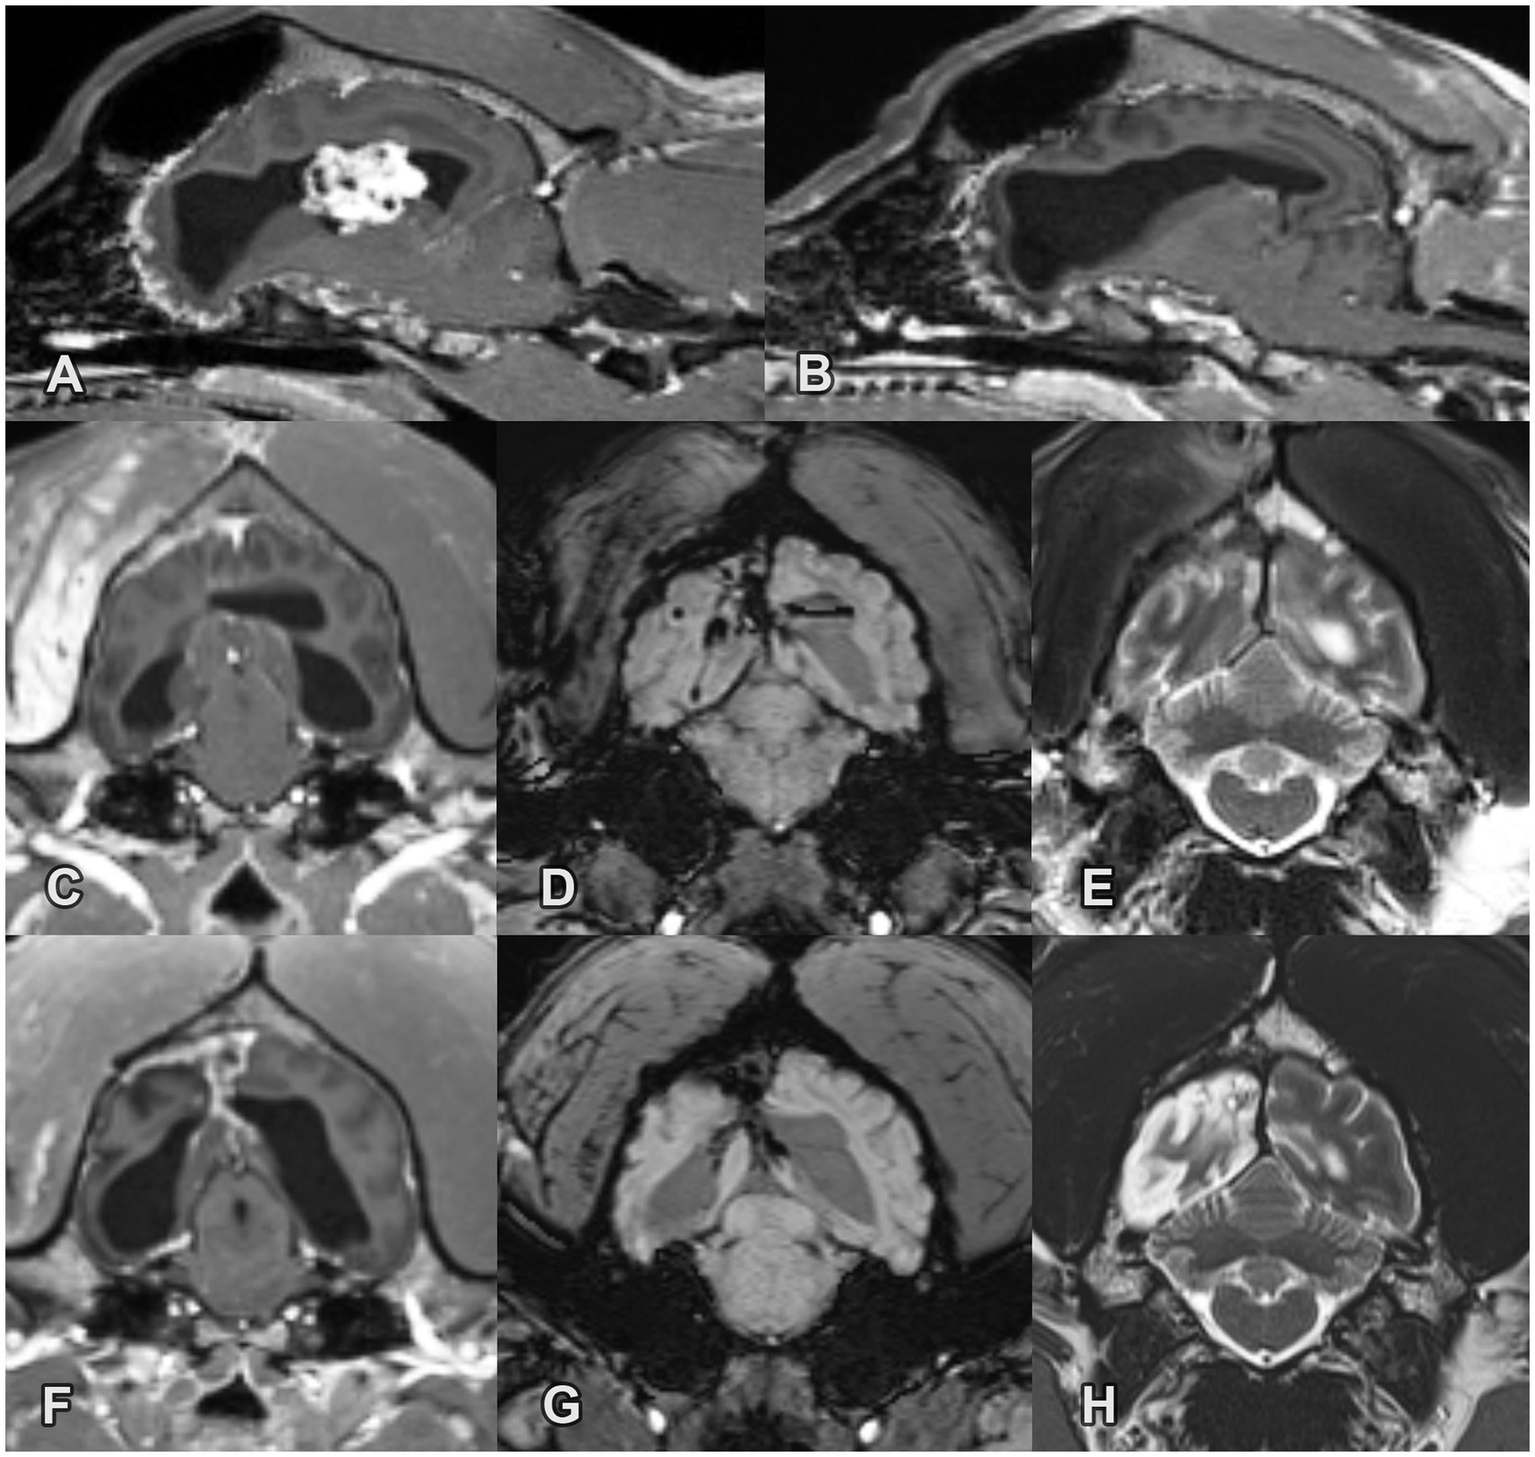

Figure 1

Pre- and post-operative MRI images of a choroid plexus papilloma in the right lateral ventricle in Case 1. (A) Pre-operative sagittal T1W post-contrast image. Note the large cauliflower-like mass with marked contrast enhancement and the secondary moderate chronic ventriculomegaly. (B) 1-month post-operative sagittal T1W post-contrast image. The mass is no longer present. The lateral ventricles remained moderately enlarged without significant change compared to the pre-operative status. (C) 1-month post-operative transverse T1W post-contrast image. Note the marked contrast enhancement along the site of the surgical approach in the right temporal muscle, calvarium and falx cerebri. (D) 1-month post-operative transverse SWI image. Signal void is present along the site of the surgical approach consistent with moderate subacute hemorrhage. (E) 1-month post-operative transverse T2W image. The sulci are mildly widened in the right occipital lobe. (F) 17-month post-operative transverse T1W post-contrast image. The lateral ventricles remained moderately enlarged without significant change compared to the pre-operative status. The contrast enhancement decreased in the temporal muscle but remained static in the brain. (G) 17-month post-operative transverse SWI image. The area of the signal void is mildly decreased. (H) 17-month post-operative transverse T2W image. Note the progressive atrophy of the right occipital lobe.

Two 5-min-long generalized tonic–clonic seizures (GTCS) occurred within 1 month of tumor resection. In the following 3 months, no epileptic seizures were observed, and the dog was in good condition without neurological deficit. Two GTCS occurred 4 months after the intervention. After increasing the ASM dosage, no further seizures were observed for 6 months. Ten months after surgery, the dog started to show 2–3 focal seizures every 2–3 months. Two GTCS occurred 12 months later. The levetiracetam dosage was increased from 20 mg/kg to 30 mg/kg TID, PO, and phenobarbital was administered as an add-on ASM (2 mg/kg BID, PO). Three years and 5 months after surgery the dog had approximately 2–5 min long focal epileptic seizures every 3–4 months and has still visual deficit. To date, the dog has undergone 3 follow-up MRI scans (1, 5, and 17 months after surgery). No additional MRI has been conducted because the owner has declined until the dog shows clinical signs of deterioration. Remnants of the mass or recurrence were not detected. The lateral ventricles remained moderately enlarged without significant changes compared to their pre-operative status. Moderate subacute hemorrhage and contrast enhancement were observed at the surgical site on the first MRI scan. The area of the signal void was slightly decreased in the follow-up MRI. The contrast enhancement remained static in the brain. Progressive atrophy of the right occipital lobe was observed on the second and third MRI scans (Figures 1B-H).